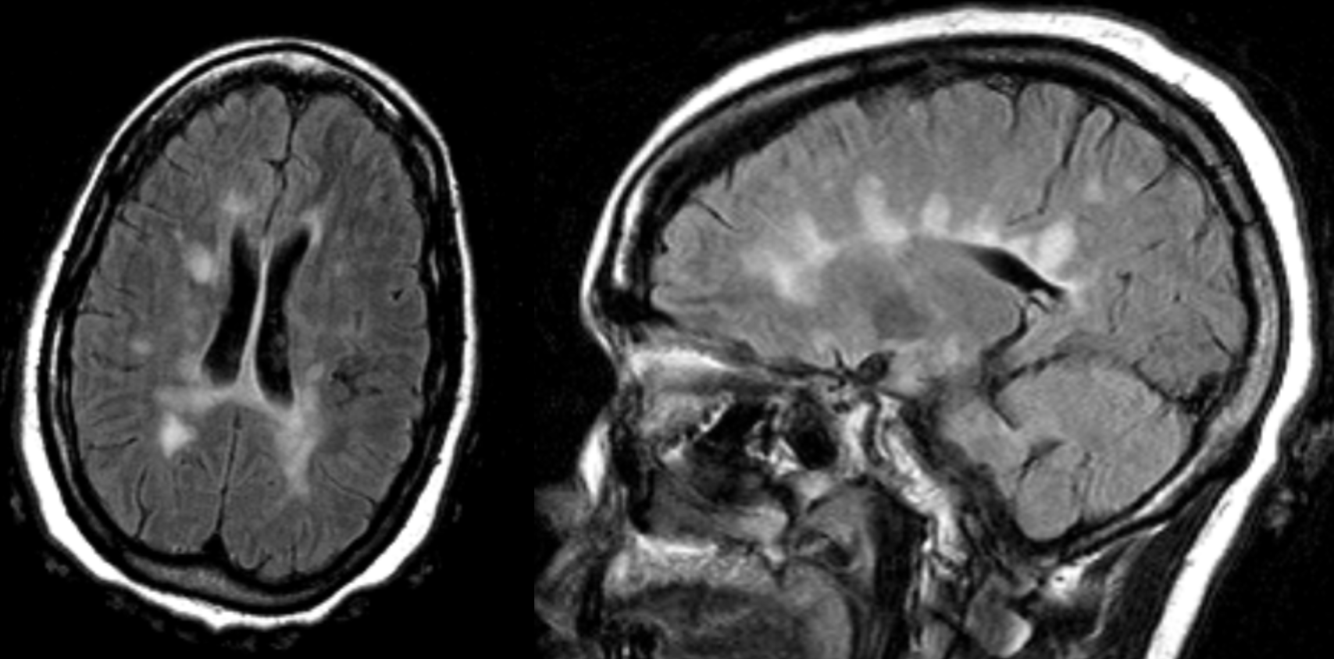

A 30 year-old female presented with with double vision.

Multiple sclersois - Dawson’s fingers